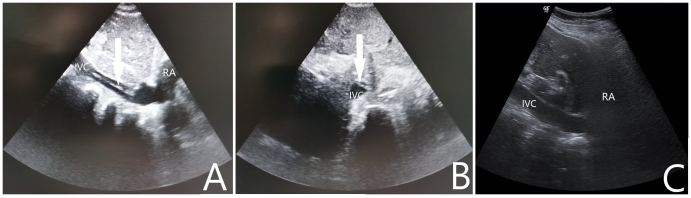

1 一般资料病例1:女性,68岁,农民,既往有“高血压病”“扩张型心肌病”“左束支传导阻滞”史,未规律诊治。主诉“突发意识不清1.5 h”于2021-02-07入院。入急诊时心搏呼吸未闻及,予高级生命支持,心电监护提示室颤,除颤治疗无效,征得家属同意后行机械按压下ECMO支持。超声引导下V-A模式上机,ECMO参数设定:转速3 500 r/min,流速3.3 L/min,吸入氧浓度(FiO2) 100%,气流量3 L/min。ECMO成功转机后停止胸外按压,患者出现ROSC,复查床旁心电图提示“右束支传导阻滞”。患者转运至介入室行经皮冠脉造影提示左右冠主干及各支未见病变,行头颅CT、胸腹主动脉CTA检查未见明显异常,考虑本次系扩张型心肌病合并双侧束支传导阻滞引起心搏骤停,予安置临时起搏器。ECMO上机后共使用肝素3 000 U,返回急诊ICU后给予全身肝素化抗凝,每2 h监测一次活化部分促凝血酶原激酶时间(activated partial thromboplastin time,APTT),目标APTT维持在60~80 s。入院后第1天患者出现消化道出血、穿刺处大量渗血、ECMO流量不稳定,血常规提示血红蛋白进行性下降,心脏彩超检查提示左室腔55 mm,左心室射血分数(left ventricular ejection fraction,LVEF):21%,左室壁运动普遍弥漫性减弱,给予输红细胞悬液6 U、新鲜冰冻血浆2 900 mL并调整肝素抗凝强度使得APTT维持在50~60 s。入院后第3天患者消化道出血及穿刺处渗血好转,停血管活性药物,未再发恶性心律失常。入院后第4天撤除ECMO,撤机前ECMO参数设定:转速2 250 r/min,流速1.8 L/min,吸入氧浓度40%,气流量3 L/min。入院后第5天心脏彩超提示LVEF:39%,同时发现下腔静脉距离右心房入口4 cm左右有附壁血栓形成,长约1.09 cm,宽0.5 cm,随血流飘动(如图 1A所示),筛查下肢其他部位未见明显血栓形成,遂给予依诺肝素钠100 IU/kg皮下注射每12 h一次治疗。入院后第7天行超声检查下腔静脉未见明显异常回声(如图 1B所示),考虑抗凝治疗后血栓消失。住院期间患者未出现过下腔静脉综合征或肺栓塞的症状或体征。经过后期的心肺康复治疗患者于2021-03-11出院,意识水平恢复正常,遗留双下肢肌力下降。

| A:箭头显示超声下在下腔静脉处附壁漂浮的血栓;B:经治疗后超声在下腔静脉未见明显异常回声;RA:右心房,IVC:下腔静脉 图 1 撤离ECMO 1 d后行下腔静脉超声检查 |